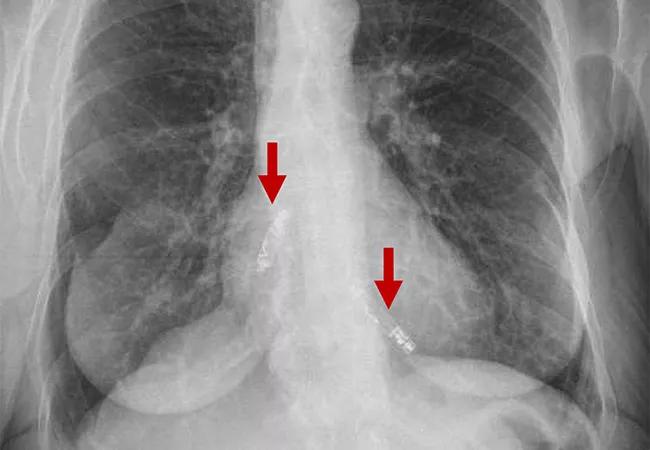

imaging study showing two leadless pacemakers in upper and lower chambers of heart

In the trial, two miniaturized leadless pacemakers were independently implanted into the heart’s upper and lower chambers via a catheter through the femoral vein and were able to provide beat-to-beat wireless communication to synchronize the heart’s pumping action.